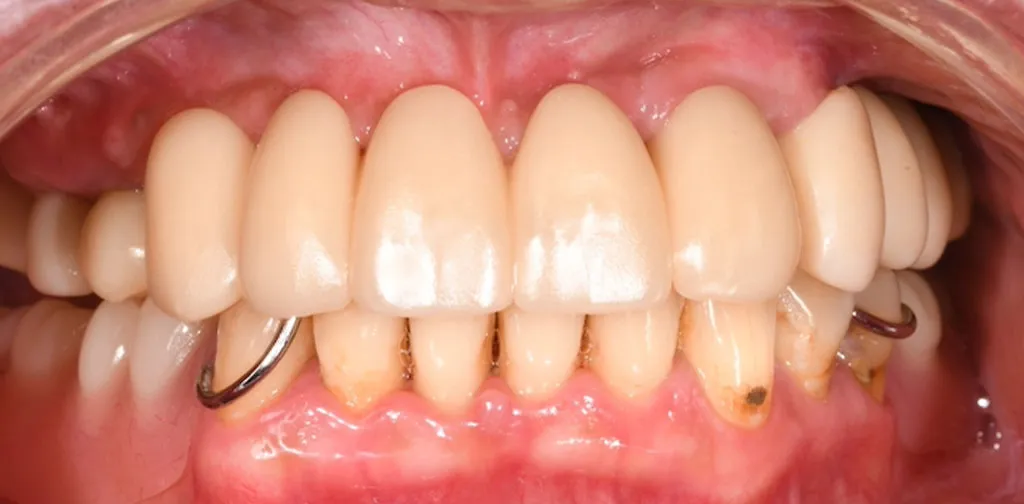

Before

After

複数本のインプラント治療

50代女性

治療期間:4ヶ月

費用:総額120.4万円(検査・診断・手術関連処置費用等を含む)

リスク:出血、腫脹、疼痛、神経麻痺、補綴物の脱落、破折、インプラント体の破折、咬合違和感、インプラント周囲炎など